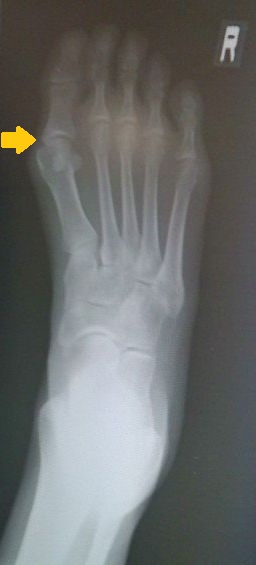

レントゲン撮ってもらった。

先生が来る前にこっそり写メで撮ったので画像悪いです。

骨が若干ずれてるのがわかる。

先生曰くそんなにひどくないって。

ひどい人は親指が人差し指にかぶってるらしい。